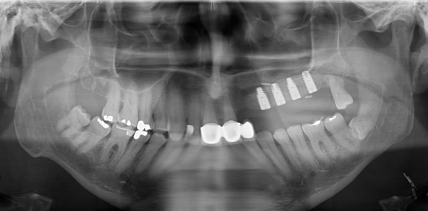

DVT-Diagnostik bei -Gefäßstielverknöcherung nach -Fibula-Transplantation

Jahr 2015, Ausgabe 03, Seite 20 Autoren: Daniel Kärcher, Christian Dinu, Dr. Dr. Eva Gudewer, Dr. Jörg Mudrak, Priv.-Doz. Dr. Dr. Lei Li